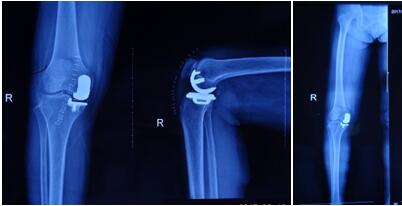

近日骨科在張富軍主任帶領(lǐng)下,在保膝理念的驅(qū)動(dòng)下,成功開(kāi)展我院首例生物單髁膝關(guān)節(jié)置換術(shù),更是全國(guó)第9例,西北地區(qū)第2例。這意味著本次手術(shù)在西安市內(nèi)乃至整個(gè)西北地區(qū)都極為罕見(jiàn),我院在骨關(guān)節(jié)病診治技術(shù)邁上了新的臺(tái)階,為膝關(guān)節(jié)炎患者提供了一種新的選擇。

提起膝關(guān)節(jié)置換術(shù),多數(shù)病人起初都是拒絕的,至少在單髁置換術(shù)出現(xiàn)之前,不乏有“談虎色變”的患者,而這些患者普遍遺留這樣一個(gè)問(wèn)題:能否僅置換部分磨損的關(guān)節(jié),保留大部分自體關(guān)節(jié),用更小的創(chuàng)傷解決痛苦呢?答案是肯定的,隨著科技的進(jìn)步和手術(shù)技術(shù)的精湛,單髁關(guān)節(jié)置換應(yīng)運(yùn)而生,成為近2年風(fēng)靡一時(shí)的手術(shù)方式,術(shù)中要求精確至1mm,其具有創(chuàng)傷小,恢復(fù)快,骨長(zhǎng)入理想,骨質(zhì)保留量大,本體感覺(jué)不破壞的優(yōu)勢(shì)。目前膝關(guān)節(jié)單髁置換多為骨水泥型,生物型全國(guó)僅開(kāi)展9例。生物型作為全新的置換方式比骨水泥型更具有突出的優(yōu)勢(shì),逐漸成為新的趨勢(shì)。